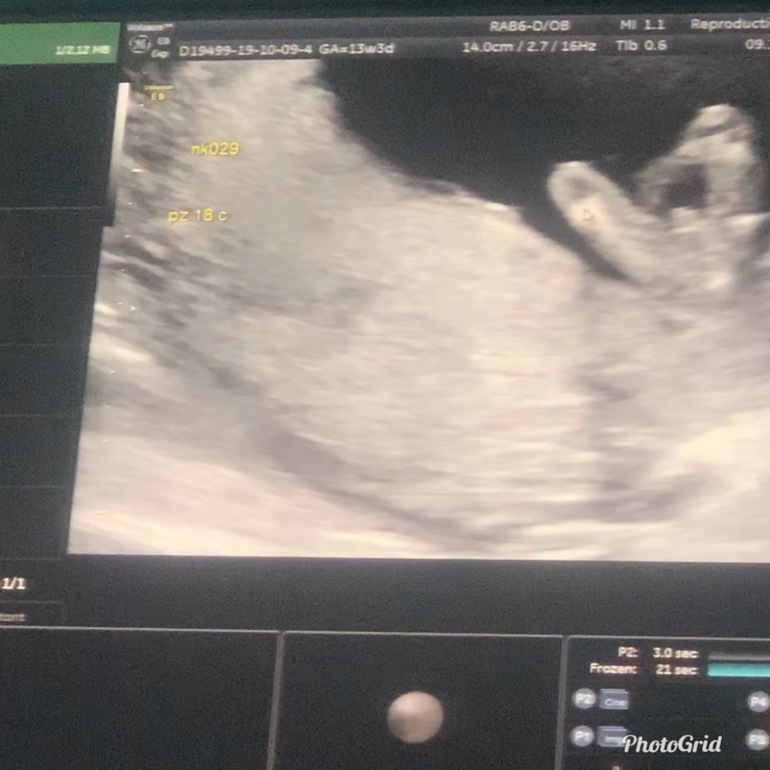

Узи 14 недель и пол

Пол малышаИ у нас будет мальчик 🙏🏼 Будут у нас три богатыря 🙏🏼🙏🏼🙏🏼😌 на самом деле я рада и очень горжусь ! Буду единственная девочка в семье ))) Добавлю фото с узи , сбоку где там половой Богорок я не поняла , а снизу показали ) По мес срок 13.3 по узи Ктр 81 на 14 недель ! Все хорошо 👌🏽 Ходила смотрела тонус и шейку , улетаем на днях 🙏🏼От всех получила добро на перелёт !

И снизу

На втором фото видно половой бугорок!